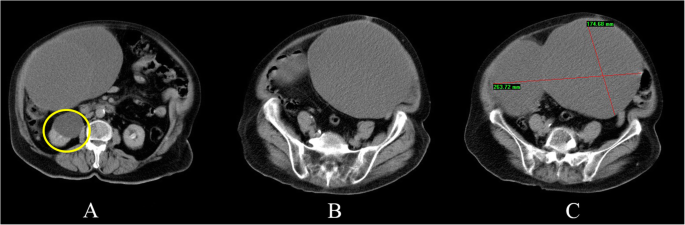

A 67-year-old woman presented to the emergency department at our university hospital complaining of constipation and right flank pain. She suffered from uncontrolled hypertension and type 2 diabetes mellitus. Additionally, the patient claimed that she was diagnosed with an adnexal cyst 7 years ago. Her previous gynecologist did not manage to determine exactly whether the cyst was ovarian or abdominal in origin and no further surgical interventions or sonographic imaging follow-up were carried out. On presentation, the patient was hypertensive and tachycardic. She was afebrile and her oxygen saturation was normal. Upon clinical examination, her abdomen was distended and non-tender. Her cardiac auscultation revealed arrhythmic arrhythmia. The laboratory tests were unremarkable except for a raised blood glucose level of 201 mg/dL. Her complete blood count, electrolytes, liver and kidney function tests were within the normal limits. A 12-leads electrocardiogram revealed atrial fibrillation with rapid ventricular response. A computed tomography scan (CT scan) of the abdomen revealed the presence of a large multilocular cystic mass measuring 17 X 26 cm in its anterior-posterior and transverse diameters respectively. The cyst occupied most of the abdomen and caused bowel obstruction and right sided hydronephrosis (Fig. 1).